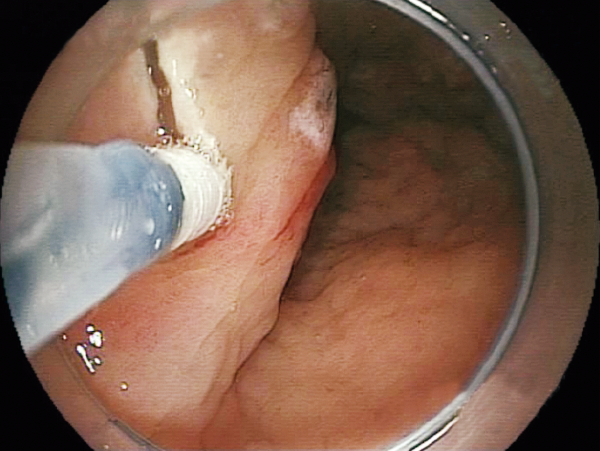

Clinical Image :Marking

Clinical Image :Water jet

Clinical Image :Mucosal Injection

Clinical Image :Submucosal dissection

Clinical Image :Submocosal injection

Clinical Image :Coagulation